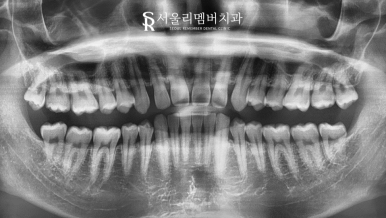

초진 사진을 보면 한눈에 봐도 아랫니가 거의 보이지 않을 정도로

수직 피개량이 크게 나타나고 있는 것을 볼 수 있었습니다.

이와 더불어 골격성 2급 부정교합으로 판단이 되었는데요.

수직, 수평 피개량 모두 크게 나타나 있는 상황이라 하루빨리 치아교정을 통해

현재 나타난 문제들을 개선하는 것이 좋겠다는 판단이 들었습니다.

문제는 여기서 끝이 아니었는데요.

하악 악궁을 살펴보면 둥근 형태가 아닌 약간 V자 형태의 모습을 갖고 있습니다.

이곳도 전체적인 개선을 통해 말발굽의 형태로 만들어주어 더 나은 교합을 갖게 해야겠네요.

과하게 물리던 앞니의 모습은 사라지고 정상 피개량으로 개선이 되었습니다.

또한 악궁 및 배열 상태도 전에 비해 더 긴밀하게 바뀐 것을 볼 수 있었는데요.